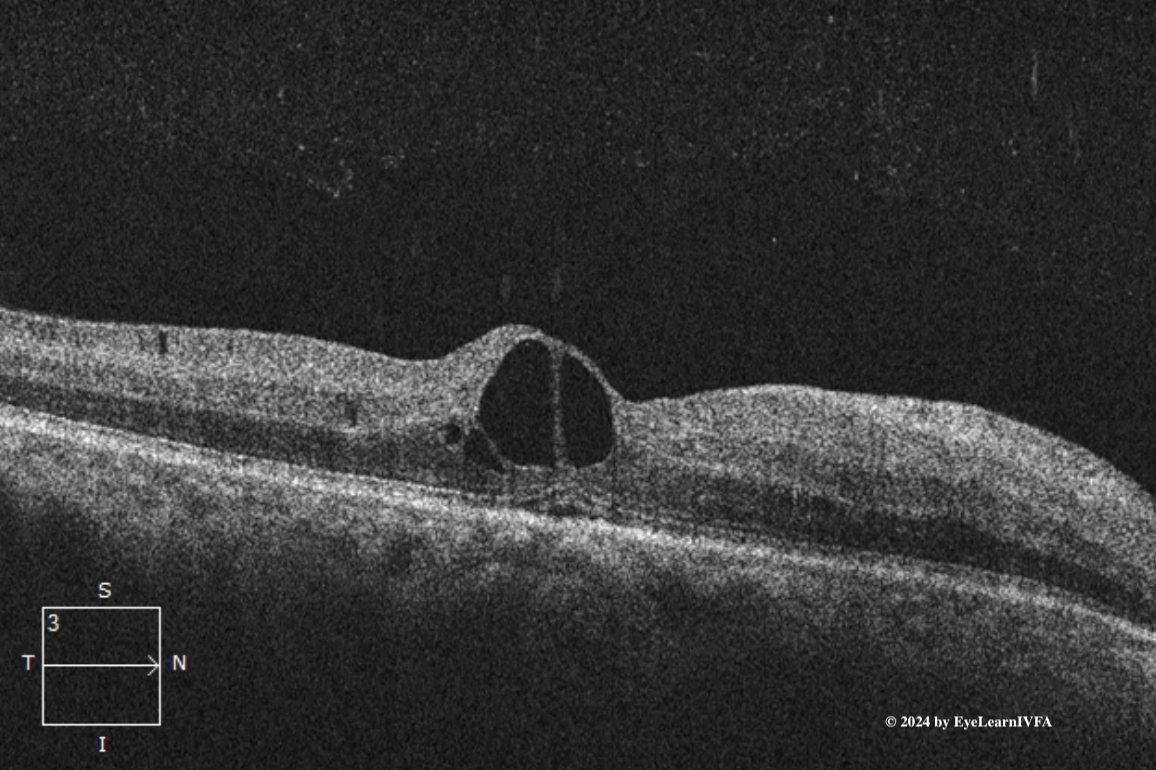

• This IVFA demonstrates a pattern consistent with high risk proliferative diabetic retinopathy. This is characterized by areas of hypofluorescence from retinal ischemia and hyperfluorescence associated with NVE and NVD.

Additional features of PDR are evident, including IRMAs, MAs. High risk features include the presence of NVE, NVD and and evidence of vitreous hemorrhage.

• IVFA is an important diagnostic tool in the evaluation and management of PDR. It allows for precise detection of neovascularization, including both clinically apparent and subclinical NVE and NVD that may not be fully appreciated on dilated fundus examination. Additionally, IVFA delineates areas of capillary non-perfusion and retinal ischemia, which are key indicators of disease severity. This information is essential for guiding targeted focal laser therapy, assessing the need for and monitoring response to anti-VEGF treatment, and determining the extent and urgency of pan-retinal photocoagulation (PRP).